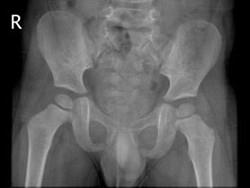

男,请根据其正常盆腔影像图像,判断其最可能的年龄 ( )A、3岁左右B、9岁左右C、12岁左右D、6岁左右E、15岁左右

问题 男,请根据其正常盆腔影像图像,判断其最可能的年龄 ( )

选项 A、3岁左右 B、9岁左右 C、12岁左右 D、6岁左右 E、15岁左右

答案 A